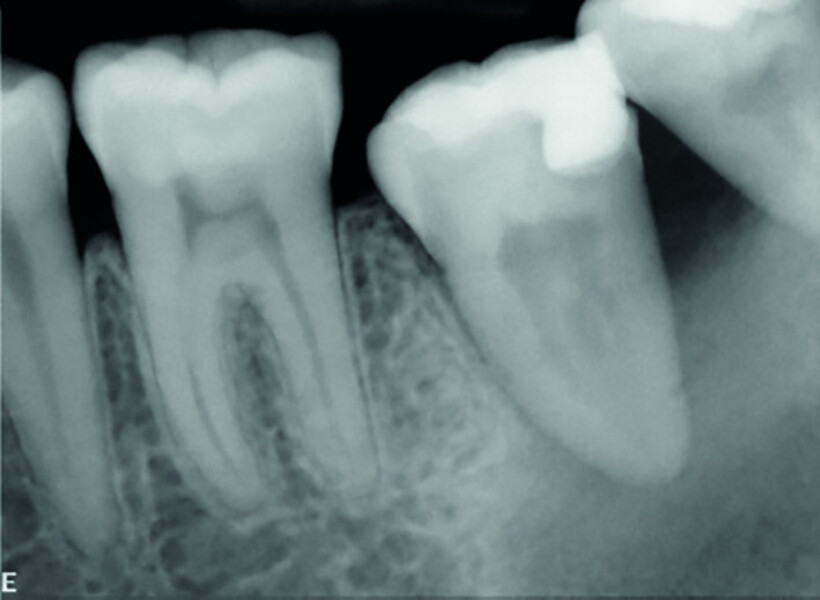

Fig. 3: Pre-op periapical radiograph.